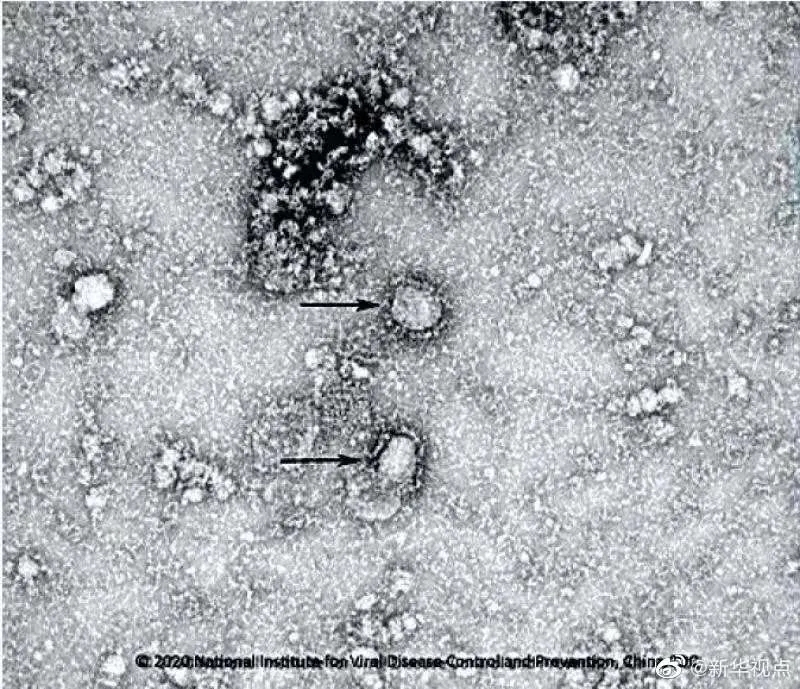

王延轶:这种说法完全是无中生有的。因为武汉病毒所最早是在去年的12月底,12月30号,才第一次接触到,当时还是叫不明原因肺炎的临床样本,后来也是经过了这种病原检测的工作,我们才发现这些样本里面其实含有一种以前完全未知的一个全新的冠状病毒,也就是我们现在说的新冠病毒。

在这之前我们是完全没有接触过、研究过或者保存过这种病毒,实际上我们也和大家一样,都不知道这种病毒的存在。所以你都没有的东西你怎么去泄漏它呢?

王延轶:您提到的这个和新冠病毒基因组相似性达到96.2%的蝙蝠的冠状病毒有一个名称叫做RaTG-13。可能在普通人看来,96.2%的相似性已经非常高了,但冠状病毒它其实是基因组最大的RNA病毒之一。所以拿新冠病毒举个例子,它全基因组有3万个碱基左右,3.8%的区别的话,其实对应的就是1100多个位点的这种差异。在自然界里面,病毒它要通过自然进化累积到这样一个数量突变的话,其实需要一个很漫长的过程。而且近期我们注意到应该说是全球病毒进化的一个顶尖学者,Edward Holmes他发了一篇声明,就认为RaTG-13的话在自然界也需要50年左右的时间才可能进化到新冠。而且你想就是1100多个位点的不同数量本身已经很大,然后这些位点还刚好都要对应到新冠病毒的相应的位点上,就刚刚好是这些1100个位点发生突变,并且刚刚好变成新冠病毒的样子,所以这里面的概率可以说是微乎其微的。 可能很多人都会有一个误解,就认为既然武汉病毒所报道了RaTG-13和新冠病毒基因组的相似性,那么你武汉病毒所就有这种病毒,但实际上不是这样的。我们只是在对蝙蝠样本进行测序的过程中,知道了RaTG-13病毒的序列信息,但我们并没有去分离和获得过RaTG-13活病毒,所以也就不存在泄漏RaTG13的这样一个可能。

王延轶:就像您刚才提到的武汉病毒所的一些研究团队,比方说石正丽老师的团队,他们从2004年就开始从事蝙蝠(SARS样)冠状病毒的相关研究,但是他们的研究都是围绕着SARS溯源这么一个主题所开展的。在他们研究过程中,他们更多地去关注的,更深入地去研究的以及更希望去分离获得的,都是和SARS比较相近的这种蝙蝠冠状病毒。我们知道这一次的新冠,其实它和SARS全基因组的相似性也只有80%,可以说还是有比较明显的差别。所以在石老师以往的研究过程中,就没有关注这种和SARS的相似性相对比较低一些的病毒,这就是为什么他们一开始没有尝试要去分离获得RaTG13,(和SARS)基因组的相似性也只有百分之七十九点几。这么多年下来,其实石老师他们确实分离获得过一些蝙蝠的冠状病毒,应该我们目前一共有三株。但是这三株病毒和SARS的相似性最高的有96%,但是和新冠病毒的相似性最高的都不超过79.8%。CGTN:因为我们病毒所长期以来,自从SARS以后就致力于冠状病毒的研究,我们可以说是深入到很多地方去找这个病毒,那么我们这次新型冠状病毒爆发了以后,这样一个全新的病毒,我们对它的溯源又做了哪些工作?